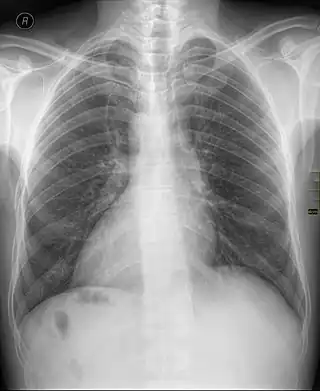

Dextrocardia (from Latin dextro, meaning "right hand side," and Greek kardia, meaning "heart") is a rare congenital condition in which the apex of the heart is located on the right side of the body, rather than the more typical placement towards the left.[1][2]

Dextrocardia situs inversus refers to the heart being a mirror image situated on the right side. For all visceral organs to be mirrored, the correct term is dextrocardia situs inversus totalis.[5][6]